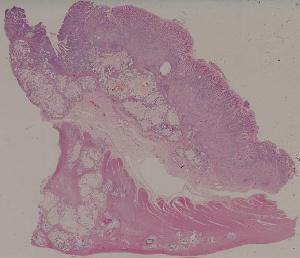

61.胃腺癌(胃粘液腺癌)

友情链接: